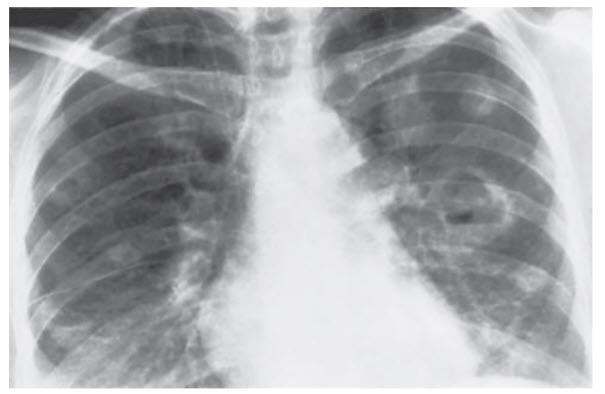

A 29-year-old woman presents to the hospital with a 3-day history of fever, night sweats, cough, and dyspnea. Her cough is productive of yellowish sputum. She denies ever having these symptoms in the past, and has no recent exposures to sick contacts. She has no significant medical history and takes no medications. She smokes 5 to 7 cigarettes daily, drinks alcohol socially, and admits to occasional illicit drug use. On examination, her temperature is 38.6°C, blood pressure is 124/76 mmHg, heart rate is 95 beats per minute, respiratory rate is 24 breaths per minute, and oxygen saturation is 97%. There is a 3/6 holosystolic murmur at the left sternal border that increases in intensity during inspiration. Her liver is enlarged and pulsatile. Some scarring and needle track marks are seen in the antecubital fossa, but there are no other skin findings and her neurologic examination is normal. Her laboratory values and chest x-ray (Figure below) are shown below:

Infective endocarditis. This patient presented with a constellation of findings that meet criteria for acute bacterial endocarditis, which is most likely caused by S. aureus in IV drug users like this patient. Diagnosis is based on the modified Duke criteria, in which the definitive diagnosis is made with any of the following criteria: two major, one major and three minor, or five minor. Major criteria include bacteremia (confirmed with blood culture) of an organism known to cause endocarditis and valve involvement (new regurgitant murmur or vegetation on echocardiogram). Minor criteria include predisposing conditions (e.g., IV drug use), fever, vascular phenomena (e.g., pulmonary emboli, Janeway lesions), immune phenomena (e.g., Osler nodes), and positive blood cultures that do not meet major criteria. This patient has one major criterion (tricuspid regurgitation) and three minor criteria (IV drug use, fever, and pulmonary emboli). Her tricuspid regurgitation is indicated by the murmur on examination and the pulsatile liver, which is virtually diagnostic of tricuspid regurgitation. There are no skin findings or renal involvement in this patient since her disease is limited to the tricuspid valve with emboli to the lungs. Cultures should be obtained and then empiric IV antibiotics should be started.

(A, B) Another infectious process may be considered given her symptoms and risk factors; however, the murmur on examination with the chest x-ray showing embolic events is much more concerning for endocarditis. PCP pneumonia will usually show diffuse interstitial infiltrates on chest x-ray. (D) Rheumatic fever is an autoimmune complication of untreated Group A Strep infection, and it typically presents with additional symptoms including arthralgias, skin rash, and chorea. It is diagnosed using Jones criteria. (E) Pulmonary embolism would show a normal x-ray or subtle findings such as pulmonary vascular congestion with wedge-shaped infarcts.